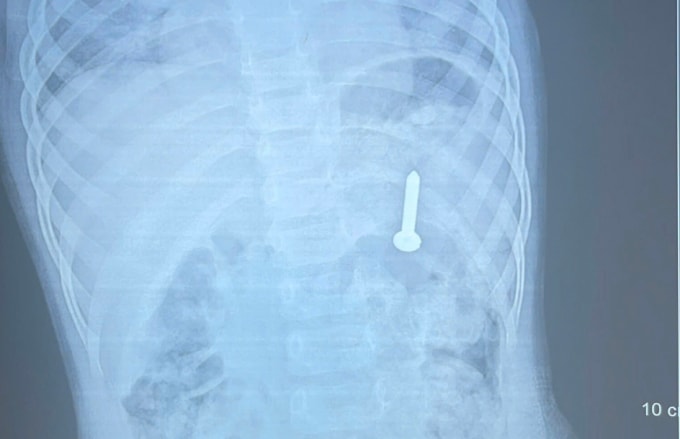

Ngày 14/4, Bệnh viện Đa khoa tỉnh Quảng Trị cho biết kết quả chụp X-quang xác định dị vật nằm trong dạ dày. Nếu không xử lý kịp thời, dị vật có thể gây thủng đường tiêu hóa, xuất huyết và nhiều biến chứng nguy hiểm.

Bé gái nuốt đinh vít dài 2,5 cm

Bé gái 21 tháng tuổi trong lúc chơi đã cầm đinh vít dài khoảng 2,5 cm cho vào miệng và nuốt phải, người mẹ vỗ lưng muốn đẩy ra ngoài nhưng trôi vào sâu hơn.